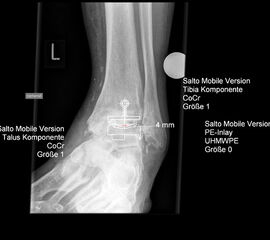

• Prothesenplanung anhand von Röntgenschablonen (Abb. 1 und 2).